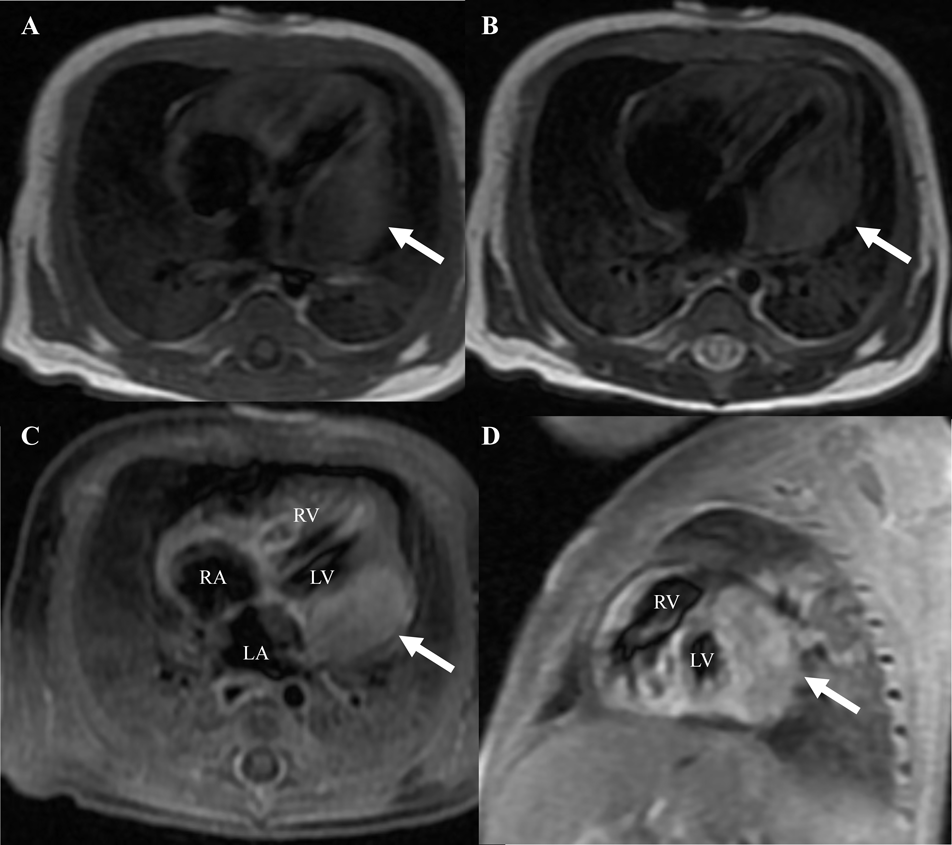

A 37-year-old pregnant woman in the 36th week of gestation (gravida 1, para 0) was transferred to our hospital due to a fetal cardiac mass noted during fetal echocardiography. Her fetal echocardiographic examination showed a large homogeneous, hypoechoic mass (24.0×16.7 mm), occupying the left ventricular cavity almost completely (Fig. 1). Other cardiac abnormalities were not detected. A male neonate was born via uncomplicated vaginal delivery at 36 weeks and 4 days of gestational age, weighing 2,896 g, the 1- and 5 minutes Apgar scores both 8. At birth it is found crying vigorously and spontaneously with good cardiorespiratory adaptation, tone and reactivity appropriate for gestational age. On physical examination, blood pressure was 58/34 mmHg, pulse regular with a rate of 132/min, breathing rate 54/min, transcutaneous oxygen saturation 94% in room air, and body temperature of 37.2°C. The initial cardiac examination revealed no significant murmur and typical facies associated with Down syndrome. Genetic testing confirmed karyotype 47, XY+21. Laboratory data, including plasma level of brain natriuretic peptide (BNP) and cardiac enzymes levels, were unremarkable. The plasma BNP level was 94 pg/mL (normal, <18.4 pg/mL). An electrocardiogram demonstrated sinus rhythm, right axis deviation, and low QRS voltage in V 5-6. A chest X-ray was negative for cardiomegaly with a cardiothoracic ratio of 0.59 but revealed a mild prominent bulge on the left cardiac border. Echocardiography revealed a large, solitary, homogenous mass contiguous with the left ventricular free wall and the left atrial wall, remarkably without evidence of ventricular systolic dysfunction (Fig. 2). There was no left ventricular inflow or outflow obstruction by Doppler interrogation. A chest contrast-enhanced Computed tomography (CT) showed a well-defined, homogenous, hypodense lesion bulging into the left ventricular and atrial cavity. No foci of calcification were identified. In addition, a CT scan of the head showed no evidence of calcification. Magnetic resonance imaging (MRI) of the chest showed a single large isointense mass in the left ventricular free wall on T1- and T2-weighted imaging. The solid component of the mass exhibited a slight enhancement following gadolinium administration (Fig. 3). Finally, these images summarized the signal intensity of nonspecific soft-tissue mass. Although we considered fibroma or rhabdomyoma would statistically be the most common etiology, tissue characteristics were not compatible with known benign or malignant masses.

Fig. 1 Ultrasound image in a fetus at 36 weeks of gestation demonstrating an oval echogenic mass (arrow) occupying much of the left ventricle

RV=Right ventricle.